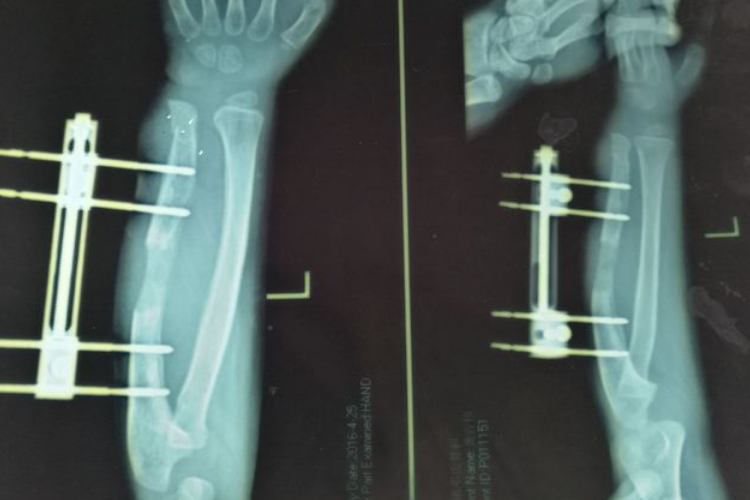

骨痂是骨延长愈合过程中新形成的连接骨折两端的骨组织,骨延长骨痂生长过程中先形成纤维骨痂再形成骨性骨痂。

在骨延长术后两周左右,由于早期大量的纤维细胞、成骨细胞等增殖活动,分泌出大量基质、成纤维细胞和成骨细胞,形成纤维骨痂,可包围并固定骨两端。

纤维骨痂形成后,成骨细胞活跃,分泌出均质透明的类骨基质,继之形成类骨组织,而后钙质在类骨基质间不断沉积形成骨组织,此时骨痂称为骨性骨痂。